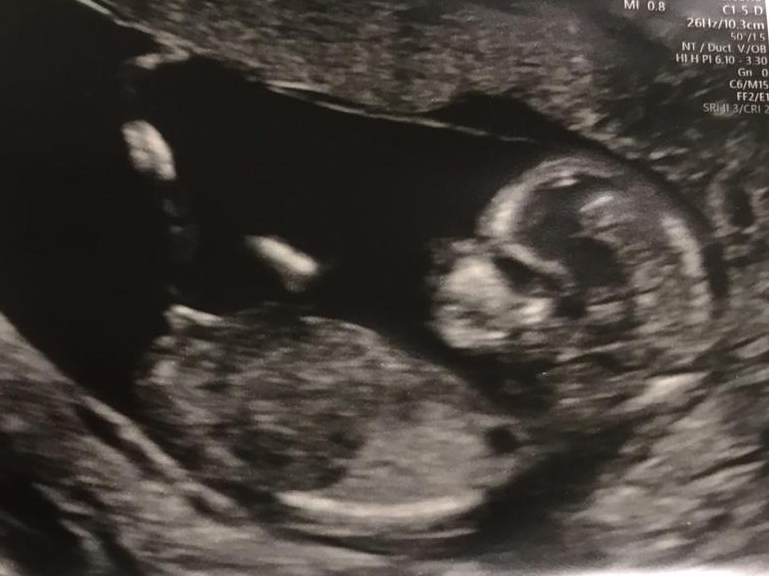

I was really lucky to have the support of family and friends so I very rarely felt lonely or alone during my pregnancy. In fact, one of the best days of my pregnancy was my 7-week scan at the clinic in London. My mum, dad, and sister Sara all accompanied me, and it was such a lovely afternoon out, which we all thoroughly enjoyed. The bonus being that Sara and I got to hear my baby’s heartbeat for the first time – such an amazing moment to share with my sister.